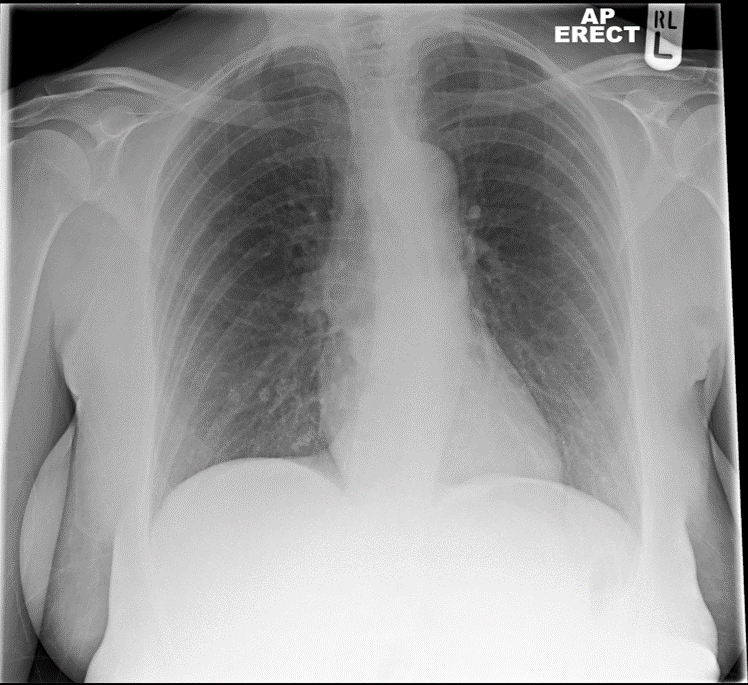

High fever, productive cough. ?ITRL

• Ill-defined consolidation (1)

• In the middle lobe of the right lung (1)

• No other abnormalities (1)